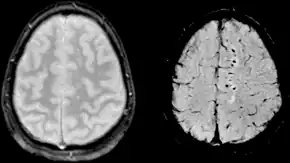

Clásicamente, la lesión traumática del cerebro se ha definido de acuerdo a criterios clínicos.[7][9] Las modernas técnicas de imagen como la resonancia magnética nuclear (RMN) muestran una sensibilidad cada vez mayor. Es posible que otros biomarcadores útiles se puedan desarrollar en el futuro.[2]

La lesión difusa se circunscribe básicamente a la lesión axonal difusa (LAD) y a algunos casos de tumefacción cerebral difusa (swelling). Una LAD es el corte de los axones en la sustancia blanca cerebral lo que causa la aparición déficits neurológicos no lateralizados como la encefalopatía. Las consecuencias de este tipo de lesión pueden tener un retraso de aparición de hasta 12 horas después del trauma. La LAD se produce por efecto de fuerzas inerciales que actúan sobre los axones durante unos 50 ms en sentido lineal o angular (por ejemplo, en colisiones frontales) lo que produce la desconexión y ruptura de los axones (axotomía primaria); no obstante la mayoría de los axones dañados (94%) son afectados por la axotomía diferida que consiste en un aumento a la permeabilidad de Ca++ en los nodos de Ranvier que causa la destrucción celular por excitotoxicidad. Ambas axotomías evolucionan desfavorablemente con cambios histopatológicos progresivos como son la formación precoz de bulbos de retracción axonal, acumulación de microglia y presencia de tractos de degeneración walleriana. La LAD puede ser identificada como hemorragias petequiales en la materia blanca (especialmente subcortical) en la TC y RM después de un TCE; sin embargo, los resultados pueden aparecer sutiles o ausentes en las imágenes. Los pacientes que padecen una LAD están subreactivos desde el momento en que se inflige el traumatismo porque la afectación axonal interrumpe las señales del sistema reticular activador ascendente y sus manifestaciones van desde una conmoción cerebral hasta la lesión axonal difusa grave.[8][5]

Usos de la Neuroimagen

La evaluación radiológica inicial es la misma que para cualquier paciente con trauma: radiografía (Rx) de tórax, de pelvis y de columna cervical.[13] El estudio de neuroimagen de elección en el TCE es TAC de cabeza sin contraste. A pesar de que el 15% de los pacientes con TBI tendrá una lesión aguda detectada por TAC sin contraste, sólo el 1% de estas anomalías requieren intervención neuroquirúrgica.[49][50] Aunque la resonancia magnética (MRI) es un 30% más sensible que la TAC para la detección de anomalías traumáticas después de un TCE, no hay evidencia que identifica mejor a los pacientes que requieren intervención neuroquirúrgica.[51]

- Resonancia magnética nuclear (RMN): Suele ser un poco más sensible que la TAC en detectar alteraciones pero tiene un costo demasiado elevado.[17]